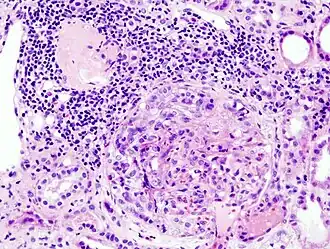

![]() Imagen histopatológica de una muestra de glomerulonefritis con semilunas obtenida de un paciente con glomerulonefritis rápidamente progresiva positiva para anticuerpos anti-MPO-ANCA. Tinción con hematoxilina y eosina. | ||

La glomerulonefritis rápidamente progresiva o extracapilar es un síndrome renal que si no se trata progresa con rapidez a una insuficiencia renal aguda y a la muerte del paciente en cuestión de meses. En el cincuenta por ciento de los casos esta glomerulonefritis se asocia con otra enfermedad de base, como por ejemplo el síndrome de Goodpasture, el lupus eritematoso sistémico o la granulomatosis de Wegener. Los casos restantes son idiopáticos, es decir, se ignora la causa de la aparición de la enfermedad. De todos modos, independientemente de la etiología principal, la glomerulonefritis rápidamente progresiva implica una serie de lesiones del glomérulo del riñón y la presencia de las típicas cicatrices con forma de semiluna en más del cincuenta por ciento de las unidades glomerulares.[1] En ocasiones, debido a esta característica histológica, la enfermedad recibe el nombre de glomerulonefritis semilunar.[1]

Pese a la gran variedad de enfermedades que causan glomerulonefritis rápidamente progresiva, todos los tipos se caracterizan por daño glomerular y formación de semilunas. El daño más grave y la ruptura de la membrana basal glomerular conducen a la pérdida de proteínas plasmáticas. De estas proteínas, se piensa que la fibrina es la que más contribuye a la formación de semilunas. Las células epiteliales que delimitan la cápsula de Bowman responden al estímulo proliferante de la fibrina. También puede haber infiltración de leucocitos como los monocitos y los macrófagos, los que también pueden proliferar bajo la influencia de la fibrina. Estas células proliferantes rodean al glomérulo y lo comprimen por lo que aparece la cicatriz con forma de semiluna que es visible con el microscopio en el material obtenido de una biopsia renal.[2]

Aunque algo arbitrario, actualmente se considera que debe de haber al menos cincuenta por ciento de glomérulos con semilunas para llamar a esta enfermedad glomerulonefritis extracapilar (crescentic).[15]

Anatomía patológica

En la biopsia de estos pacientes se halla una importante proliferación de las células epiteliales de la cápsula de Bowman, con formación de semilunas en los glomérulos.[4] La biopsia renal confirma la presencia de una glomerulonefritis con semilunas epiteliales. Entre las características histopatológicas figura la infiltración del espacio urinario por células mononucleares asociada con la proliferación del epitelio parietal de la cápsula de Bowman o la proliferación extracapilar con formación de semilunas que pueden afectar del treinta al cien por ciento de los glomérulos. En estos se ve un engrosamiento de la cápsula de Bowman con formación de semilunas. También puede haber fibrosis parcial y sinequia del penacho glomerular a la cápsula.[4] Las semilunas, que pueden ser segmentarias o circunferenciales, ocupan todo el espacio de Bowman y ahogan el ovillo capilar, según el estado evolutivo pueden clasificarse en celulares, fibrocelulares o fibrosas y representan fases progresivas del mismo proceso.[4] En la glomerulonefritis rápidamente progresiva de tipo I hay positividad lineal sobre todo para IgG pero después también para C3. Dos tercios de las glomerulonefritis semilunares de este tipo corresponden al síndrome de Goodpasture y el otro tercio carece de manifestaciones pulmonares (síndrome de Goodpasture sin compromiso pulmonar). La lesión glomerular es similar en ambos grupos y se produce por un mecanismo inmunitario antimembrana basal glomerular. Como ya se dijo, el factor desencadenante es un defecto de un componente proteico de la cadena α3 del colágeno de tipo IV.[5] En la enfermedad de tipo II hay positividad granular o nodular o de ambas formas, difusa y global, debido a depósitos de complejos inmunes que con el microscopio electrónico se ven como depósitos densos. Este tipo por lo general corresponde a variedades de la glomerulonefritis aguda difusa, de la glomerulonefritis mesangiocapilar y, menos a menudo, de la enfermedad de Berger.[5]